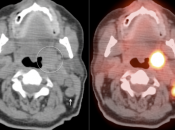

Tonsillar (Palatine) Carcinoma

- The majority of patients with tonsillar carcinoma have a biopsy-proven diagnosis prior to PET/CT scanning. In such cases, any increased FDG uptake involving a tonsil typically represents the cancer (prior to therapy).

- Many patients will present with the diagnosis of metastatic SCCA of unknown primary. A tonsillar primary must be excluded in these patients.

- Lastly, on rare occasion, an incidental tonsillar carcinoma cancer will be identified.

Symmetric, Bilateral Tonsillar Uptake:

The palatine tonsils frequently demonstrate significant metabolic activity.

Bilateral and fairly symmetric FDG-uptake in non-enlarged palatine tonsils is typically a normal finding, and is usually not mentioned in a report.

Bilateral and fairly symmetric FDG-uptake in enlarged palatine tonsils is nearly always inflammatory in nature (although can be seen with lymphoma).

Unilateral FDG-Avid Tonsil (or Relative Increased Avidity of One Tonsil):

Special care is required when assessing the incidental finding of a unilateral hot tonsil (or relative increased uptake within one tonsil) — even though most unilateral hot tonsils are benign. Proposed techniques for assessment have included SUV threshold cutoff values, metabolic tumor volume assessment, and SUV ratios.

Unfortunately, it is advisable to raise at least a degree of concern for most FDG-avid unilateral tonsillar findings. The level of suspicion, of course, depends on the presentation.